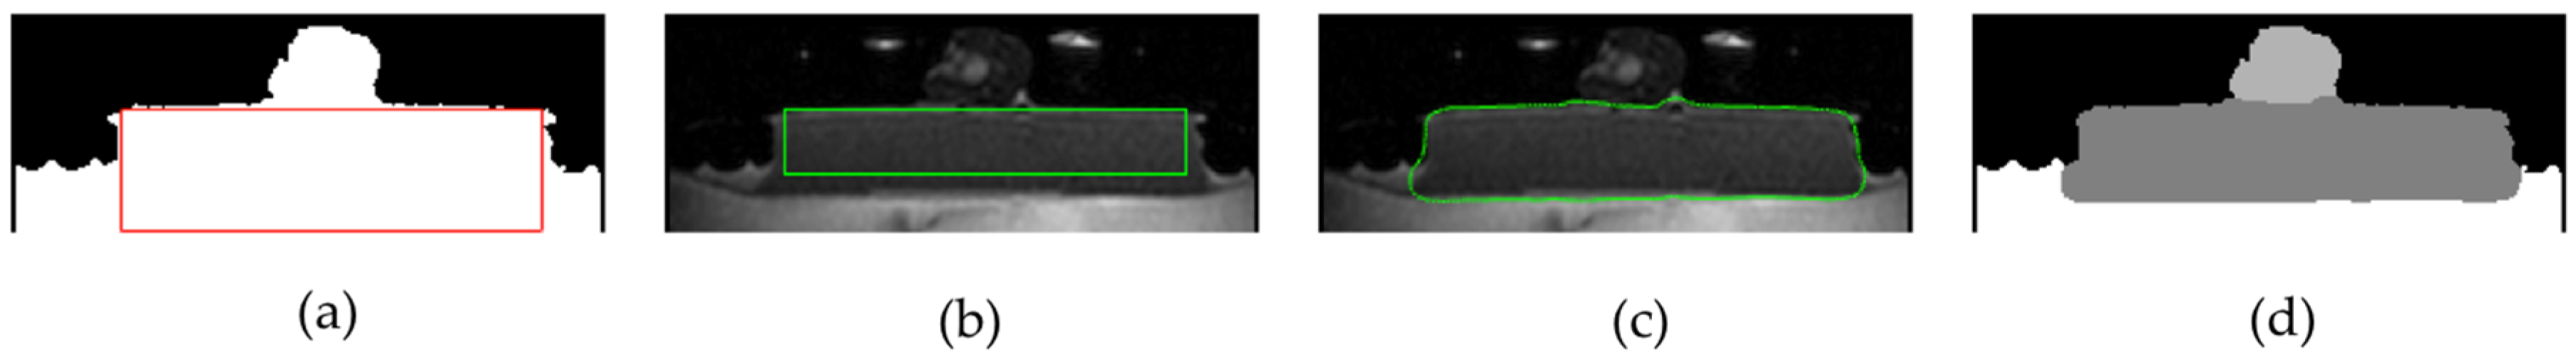

Segmentation of Gel-Pad Region

Definition of Markers for Gel-Pad and Tissue Regions